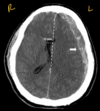

Describe

diffuse axonal injury